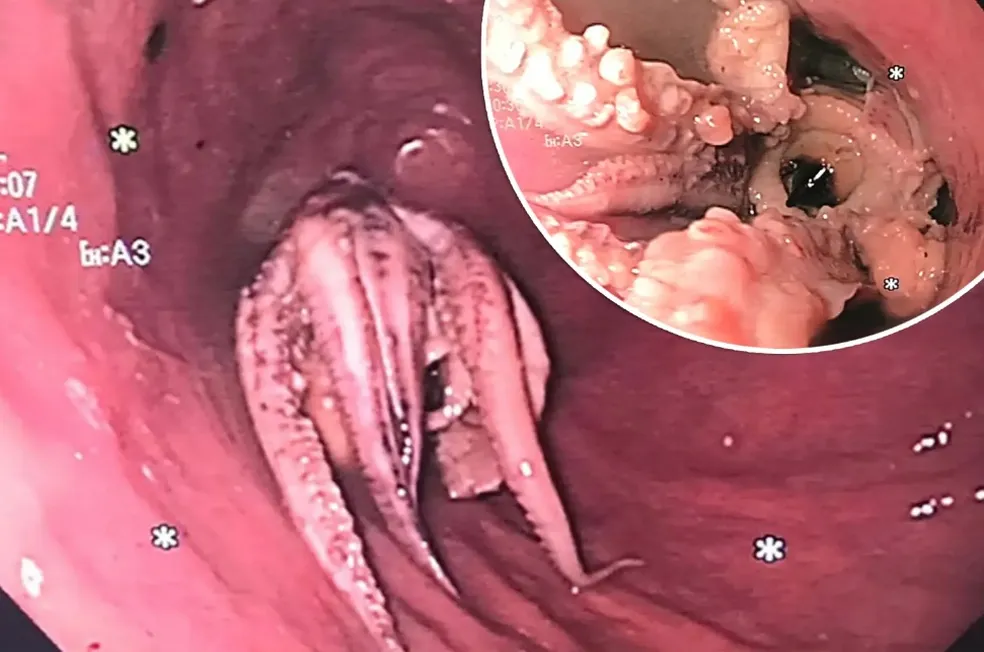

Os médicos optaram por realizar uma tomografia computadorizada, que revelou a presença de uma massa hiperdensa no esôfago do homem. Isso o levou a ser submetido a uma endoscopia digestiva alta. Durante o exame gastrointestinal, foi constatado que um polvo com tentáculos estava alojado a cinco centímetros da borda entre o esôfago e o estômago.

Após as tentativas iniciais de puxar ou extrair o molusco não terem tido sucesso, os médicos optaram por navegar o endoscópio através do polvo até o estômago e empurrá-lo para trás. Em seguida, utilizaram fórceps para agarrar a cabeça da criatura e removê-la por completo. A matéria ressalta que o paciente se recuperou bem após a cirurgia e recebeu alta após dois dias.